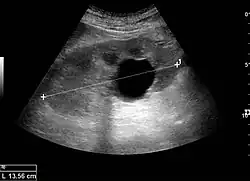

Cystic renal masses

Masses are seen as a distortion of the normal renal architecture. Most renal masses are simple cortical renal cysts with a round appearance and a smooth thin capsule encompassing anechoic fluid. The incidence increases with age, as at least 50% of people above the age of 50 have a simple cyst in one of the kidneys. Cysts cause posterior enhancement as a consequence of reduced attenuation of the ultrasound within the cyst fluid (Figure 5). The simple cyst is a benign lesion, which does not require further evaluation.[1]

Figure 5. Simple renal cyst with posterior enhancement in an adult kidney. Measurement of kidney length on the US image is illustrated by '+' and a dashed line.[1] -